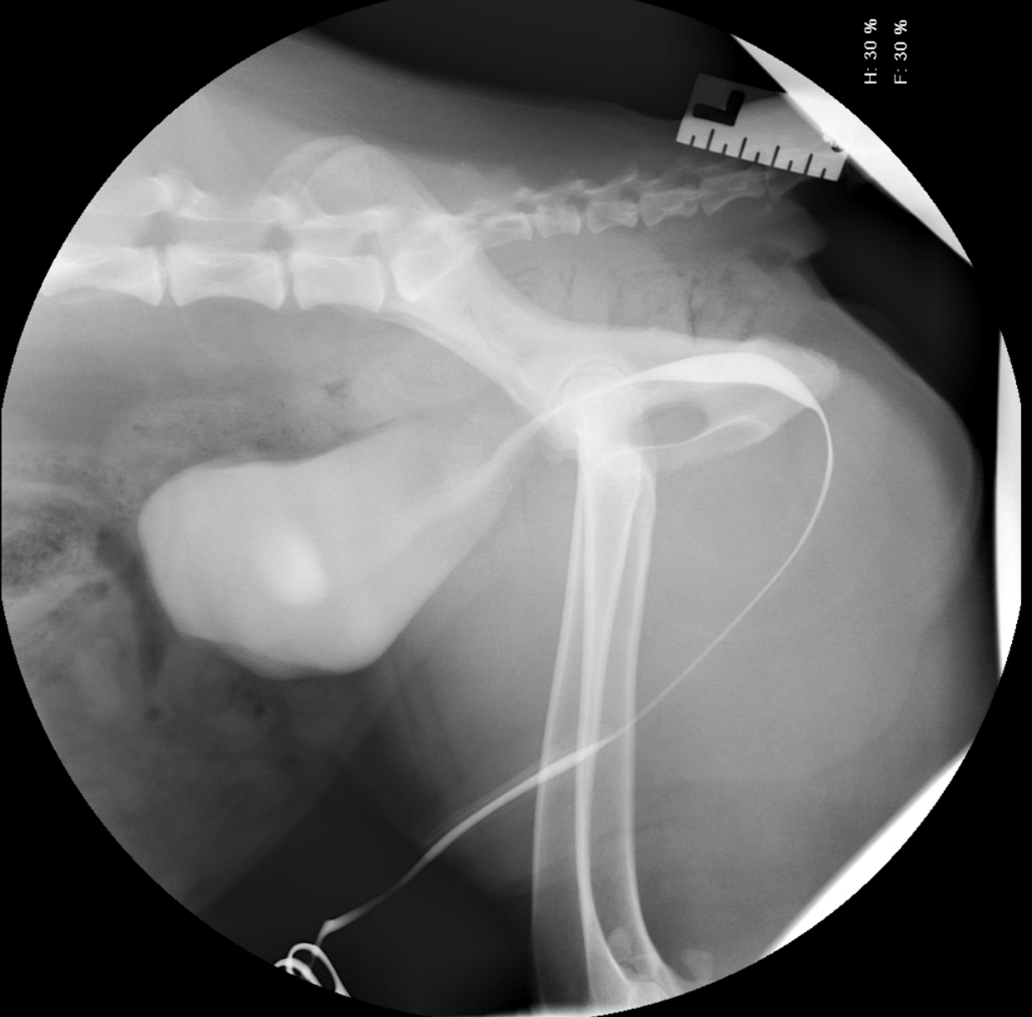

A four-and-a-half-year-old neutered male Golden Retriever presented with a one-week history of progressive stranguria at the clinic. The patient had received meloxicam 48 hours prior to referral. Physical and external urogenital tract examinations were unremarkable.

Haematology was also unremarkable, but biochemical analysis and urinalysis confirmed severe renal azotaemia (Figure 1). Abdominal ultrasonography failed to identify an underlying cause for the patient’s profound stranguria, and a contrast enhanced retrograde urethrocystogram was performed. This was unremarkable, and the patient was diagnosed with reflex dyssynergia (Figure 2).

The renal azotaemia and acute kidney injury were thought to be secondary to meloxicam therapy and urethral obstruction. Meloxicam was discontinued, and the patient was hospitalised with intravenous fluid therapy. An indwelling urinary catheter was placed for in-hospital management while tamsulosin and diazepam therapy were started. An immediate response to therapy was noted, and the patient recovered fully. Medical management was discontinued nine weeks after presentation.